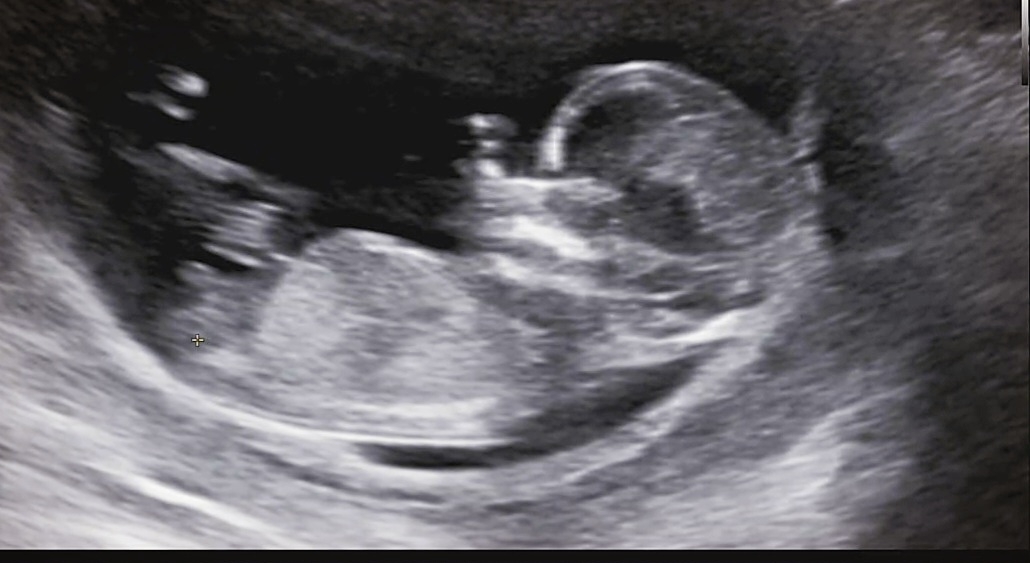

긱도로봐선 딸인데 생식기쪽 끝이 뭉툭한게 아들같아용 저는 딸로나왔는데 끝이 갈라져있거든요!! 아들은 생식기쪽이 동글동글(?)하고 딸은 살짝 갈라져있어요 ㅎㅎ

성별한번만 봐주세요 어느분은올라가있다고 하고 어느분은 내려가있다고 하고 척추뼈랑 11자 직선 나오면 딸아닌가용? 12주 4일차 입니당!

다른사진도 여러장 있으시면 올려보세요! 한장으론 판단하기 어렵네용 ㅠㅠ저 사진으론 각도는 딸인데 생식기모양은 아들이라..